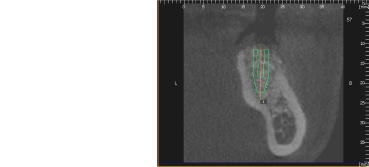

CT断層撮影では下顎管までの距離は19㎜、インプラント治療には十分な長さです。しかし、骨の断面は傾斜してえぐれているのが解ります。骨を突き抜けると大変です

CT上でシュミレーションして骨を突き破らないインプラントのサイズを決定します。

CT断層撮影で3次元的な骨の状態、血管の位置を術前に診断できます。それにより、安心、安全に治療を行えます。